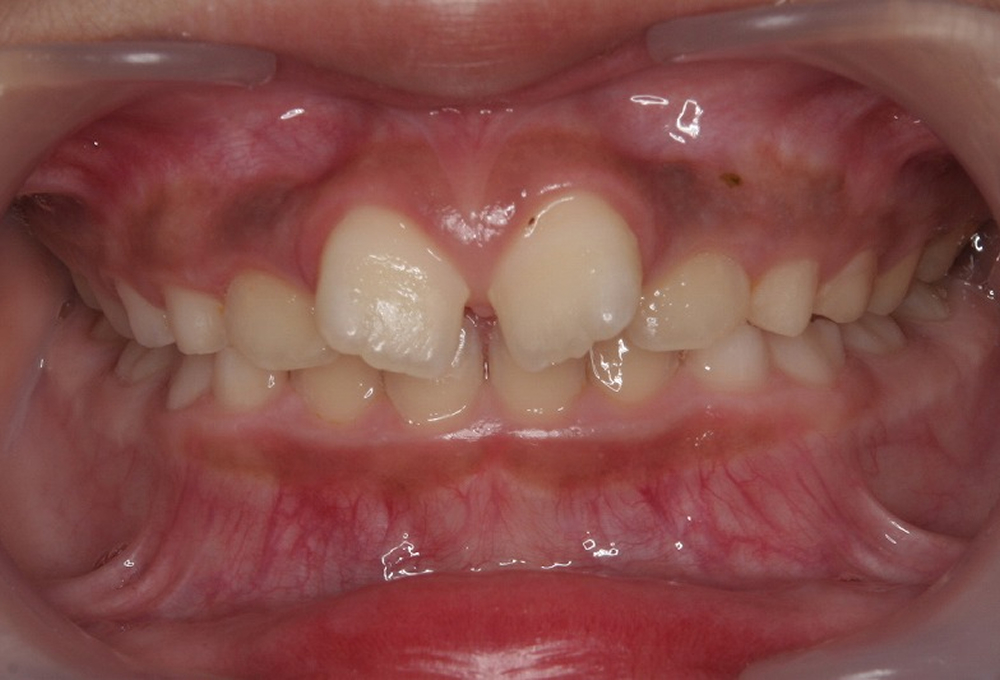

①術前 叢生